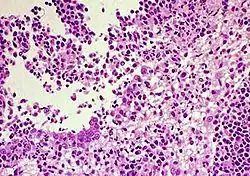

La peritonitis infecciosa felina (PIF) es una enfermedad fatal que afecta a los gatos. Algunos creen que es provocada por el virus de la peritonitis infecciosa felina (VPIF) que es un coronavirus felino. El cual sería una mutación del coronavirus entérico felino (CVEF). Aunque parece haber una conexión entre la PIF y el coronavirus felino, esto no se ha probado del todo aún. Sin embargo, la teoría más común es que el normalmente benigno CVEF puede mutar hacia el VPIF. La mutación del virus posee la habilidad de invadir y crecer en los glóbulos blancos llamados macrófagos. En respuesta, el sistema inmunitario del animal causa una intensa inflamación en los tejidos. El desenlace es generalmente fatal. Sin embargo la tasa de incidencia es aproximadamente de 1 entre 5000 para los hogares con uno o dos gatos.

Hay escasa evidencia de que el PIF (Peritonitis infecciosa felina) sea directamente transmisible de un gato a otro aunque podría explicar pequeños y raros brotes aislados de PIF.[1] Un estudio de 59 gatos infectados por PIF encontró que, a diferencia del Coronavirus felino, las heces de gatos infectados por PIF no transmitieron la enfermedad a gatos de laboratorio por vía oro-nasal.[2] El CVEF es muy común, especialmente en lugares donde grandes grupos de gatos son mantenidos juntos. Los gatos se infectan al inhalar o ingerir el virus. Las heces son la fuente de transmisión más común, aunque superficies contaminadas como platos de comida o vestimentas lo son también. A pesar de la prevalencia del CVEF, la mayoría de los gatos infectados no desarrollan el VPIF. A menudo la exposición al CVEF no produce signos clínicos, pero puede producir una leve diarrea. Por lo tanto, un gato sin signos clínicos puede seguir siendo un portador del CVEF y es capaz de transmitir el virus a otro gato. En cualquier gato infectado con el CVEF existe la posibilidad de que este mute en la forma causante de la PIF. Esta posibilidad aumenta en gatos con función inmunológica disminuida, como lo son los muy viejos o muy jóvenes.

Hay dos formas principales de la PIF: Efusiva (húmeda) y no efusiva (seca). Aunque las dos formas son igualmente fatales, la forma efusiva es más común (se da entre un 60% - 70% de los casos) y progresa más rápidamente que la forma no efusiva.

El sello clínico característico de la PIF efusiva es la acumulación de fluido en el abdomen o el pecho, lo que puede ocasionar dificultades para respirar. Otros síntomas son: disminución del apetito, fiebre, pérdida de peso, ictericia y diarrea.

La PIF seca también se presenta con disminución del apetito, fiebre, ictericia, diarrea y pérdida de peso, pero en este tipo no hay acumulación de fluido. Normalmente, un gato con PIF seca mostrará signos neurológicos característicos. Por ejemplo, podría mostrar dificultades para caminar o ponerse de pie que con el tiempo desencadenarían en parálisis. Puede haber también perdida de conciencia.